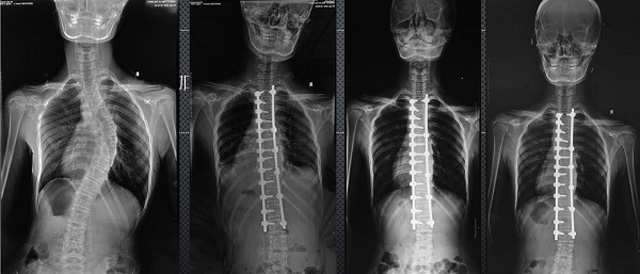

(7)全身拼接功能對有較大尺寸全脊柱拼接圖接桂成金下股分成幾次拍攝,再經(jīng)過秋件開在骨科開展的全脊柱畸形矯治工作中,雖然CT. MRI也能獲取全脊柱影像,接圖像,以便于長度、角度、力線等測量和察脊柱在重力情況下但不能進(jìn)行立位檢查,無法觀全景觀察。全身拼接功能是高等級DR攝取患者立位全下的功能狀態(tài)圖像,因此采用動態(tài)醫(yī)院特別看重的動態(tài)DR功能之一。注:圖中Cobb脊柱正側(cè)位圖像是首選的檢查方法角度的大小是反映側(cè)彎嚴(yán)重程度的一個(gè)標(biāo)準(zhǔn)。